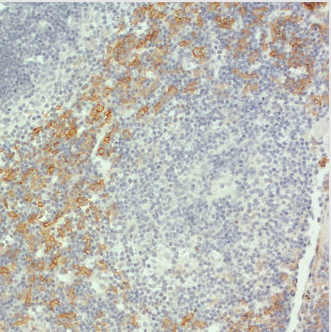

染色示例:使用生物素標記的大鼠抗F4/80抗體對小鼠脾臟切片進行染色。